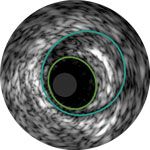

Die IVUS-Technologie von Philips liefert detaillierte Läsionsbilder, die Ihnen die Entscheidung über das optimale Vorgehen erleichtern.

Lumen

Exzentrische fibröse Plaque mit tiefliegendem Calcium

Schallschatten

Erleichtert die Dimensionierung des Geräts, um eine präzise Wandapposition, Medikamentengabe und Platzierung sicherzustellen

Verstehen Sie Art und Schweregrad der Plaque, um das richtige Gerät zu wählen

Visualisieren Sie die Position der Plaque für eine präzise Behandlung

Bestätigen Sie die Position des wahren Lumens oder des subintimalen Führungsdrahts